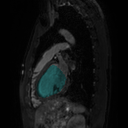

To bridge the methodological gaps when only small-scale partially labeled data is available, we propose a simple yet efficient framework Vicinal Labels Under Uncertainty (VLUU) by exploring the statistical similarity of human structures (e.g. shape, size, location) among different patients. See Fig. 1 for an illustration of such a similarity. The proposed framework is motivated by vicinal risk minimization (VRM) [11], where the fully labeled vicinal examples are generated by linearly combining randomly sampled partial labels with a weight randomly sampled from a Dirichlet distribution. These vicinal examples allow us to transform the partially supervised problem into a fully supervised one. That is to say, we can utilize any existing supervised segmentation networks and loss functions to solve partially supervised problems. The generated vicinal labels contain uncertainty regions where classes of interest could potentially overlap. We utilize these uncertainties in the training process to improve the robustness of DL models.

In standard adversarial training, the segmentation network and the discriminator play a zero-sum game. The discriminator is trained to discriminate the prediction masks produced by the segmentation network from the ground truth masks. Meanwhile, the segmentation network is trained to confuse the discriminator by producing realistic prediction masks. Adversarial training benefits from the human structure similarity as it makes the unknown true label distributions easier to be caught by the discriminator than for general objects [38]. In other words, there is smaller instance-wise variation in the size, shape, and location of human organs (or structures), as shown in Fig. 1, than for general objects.